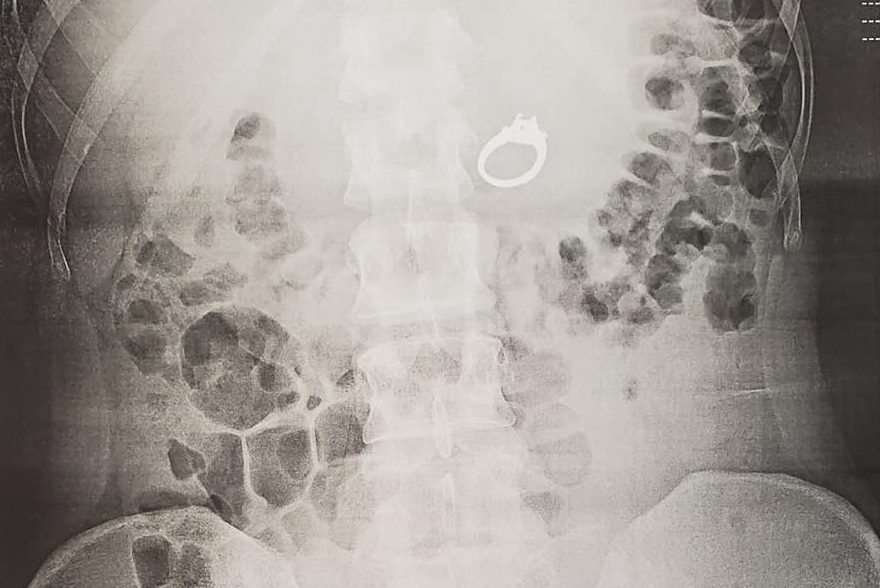

Evans says she and Howell were laughing all the way to the urgent care centre after they discovered what she’d done. However, they quickly sobered up when the doctor spotted the ring in an X-ray of her stomach and told her that it would be a bad idea to “let nature take its course.”

She shared several photos of the X-rays in her Facebook post.

A ring is shown in Jenna Evans’ stomach in this X-ray photo. Jenna Evans/Facebook